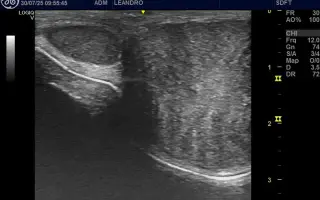

Pred mesiacom som Leovi našla tri hrčky v oblasti predkožky, ktoré sme dali hneď skontrolovať veterinárovi. Po konzultácii s veterinárom sme dospeli k záveru, že je nutné hrčky vyoperovať. Hrčky boli odstránené. Všetci sme si mysleli, že šlo o neškodný tukový nádor, no histologické vyšetrenie preukázalo moje najväčšie obavy. Zhubný nádor – fibrosarkom. Fibrosarkom je nádor spojivoveho tkaniva, ktorý takmer nikdy nemetastázuje skôr je lokálne agresívny, ale veľmi rád sa vracia.